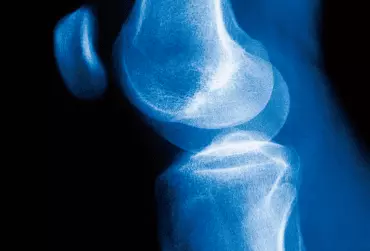

Urazy łąkotek są jednymi z najczęstszych urazów stawu kolanowego, co potwierdza liczba interwencji chirurgicznych wykonywanych rocznie zarówno w Stanach Zjednoczonych (ok. 1 mln), jak i w Europie (ponad 400 tys.) [1]. Dotychczas jedyną możliwością leczenia uszkodzeń łąkotki, które nie nadawały się do zszycia, było wykonanie przeszczepu od martwego dawcy. Naukowcom jednak udało się opracować implant, tzw. łąkotkę poliuretanową.

Współczesne poglądy na temat leczenia operacyjnego i nieoperacyjnego zerwanego więzadła krzyżowego przedniego kolana

Temat uszkodzenia więzadeł krzyżowych przednich stawu kolanowego (anterior cruciate ligament – ACL) jest tym popularniejszy, im popularniejszy staje się sport masowy. Leczenie tej kontuzji sportowej budzi od jakiegoś czasu wiele kontrowersji – operować czy nie operować? Zagadnienie to nie jest już w Polsce niszowe, bo mowa tu o kilkudziesięciu tysiącach kontuzji kolan rocznie. Patrząc na statystyki krajów bardziej usportowionych, z dużym dostępem do specjalistów, np. Stanów Zjednoczonych, można zauważyć, że liczba rekonstrukcji więzadeł krzyżowych sięga 100 000 rocznie. Warto więc ustalić, jakie są współczesne poglądy na temat rekonstrukcji ACL.

Rehabilitacja po rekonstrukcji więzadła krzyżowego przedniego metodą neoligaments – opis przypadku

Uszkodzenia więzadła krzyżowego przedniego (anterior cruciate ligament – ACL) występują często u osób młodych, prowadzących aktywny tryb życia, a szczególnie uprawiających wyczynowo lub rekreacyjnie różne dyscypliny sportowe. Są to najczęściej urazy z przeprostem i koślawieniem stawu oraz urazy powodujące rotację w stawie kolanowym [1, 2]. Zerwanie więzadła krzyżowego przedniego zaburza stabilność stawu kolanowego, prowadzi do degeneracji chrząstki i uniemożliwia uprawianie sportu. Dlatego w wielu przypadkach, a zwłaszcza u aktywnych osób, zalecana jest rekonstrukcja więzadła krzyżowego przedniego.